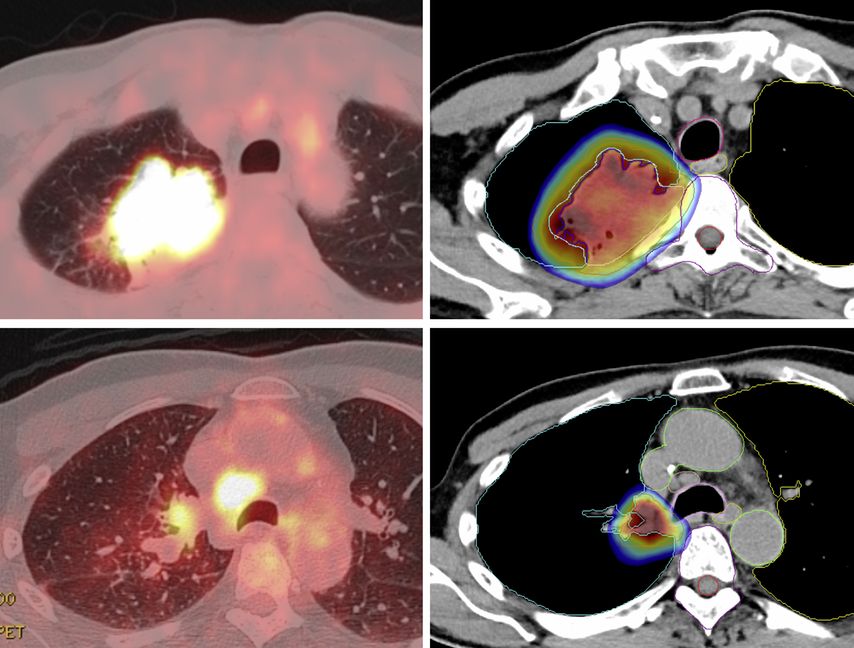

Auch die Rolle der Strahlentherapie im perioperativen Setting ist im Zeitalter der Immuntherapie erneut Gegenstand der Forschung. Aktuell untersucht die Schweizer Studie SAKK 16/18, ob eine Bestrahlung des Primärtumors das PFS nach neoadjuvanter Chemoimmuntherapie bei resektablem NSCLC im Stadium IIIA(N2) im Vergleich zur Vorgängerstudie SAKK 16/14 weiter verbessern kann.20 Die Strahlentherapie erfolgt parallel zur neoadjuvanten Immuntherapie unter Aussparung des Mediastinums, um Toxizität und immunsuppressive Effekte zu vermeiden (Abb. 2). Speziell ist zudem, dass drei unterschiedliche Strahlentherapiekonzepte randomisiert untersucht werden, um mögliche Unterschiede im Synergismus mit der Immuntherapie zu untersuchen. Interimdaten bestätigen die Sicherheit dieses Ansatzes, für den eine kleinere Studie aus China in ähnlicher Form kürzlich eine sehr hohe Rate an pathologischer Remission (MPR) von 76% präsentieren konnte.21,22

Abb. 2: Immunmodulatorische Strahlentherapie in der SAKK 16/18-Studie: Die Studie untersucht, ob eine Bestrahlung die Wirkung der Immuntherapie mit Durvalumab im neoadjuvanten Setting verbessern kann. Die Strahlentherapie erfolgt fokussiert auf den Primärtumor, wobei Normalgewebe sowie Lymphknoten im Mediastinum geschont werden. Darstellung: PET-CT (links); Strahlentherapie-Plan (rechts), Farbverlauf mit Dosis ≥20Gy im Arm B (5x5Gy). Quelle: Universitätsspital Basel (mit freundlicher Genehmigung des Patienten)